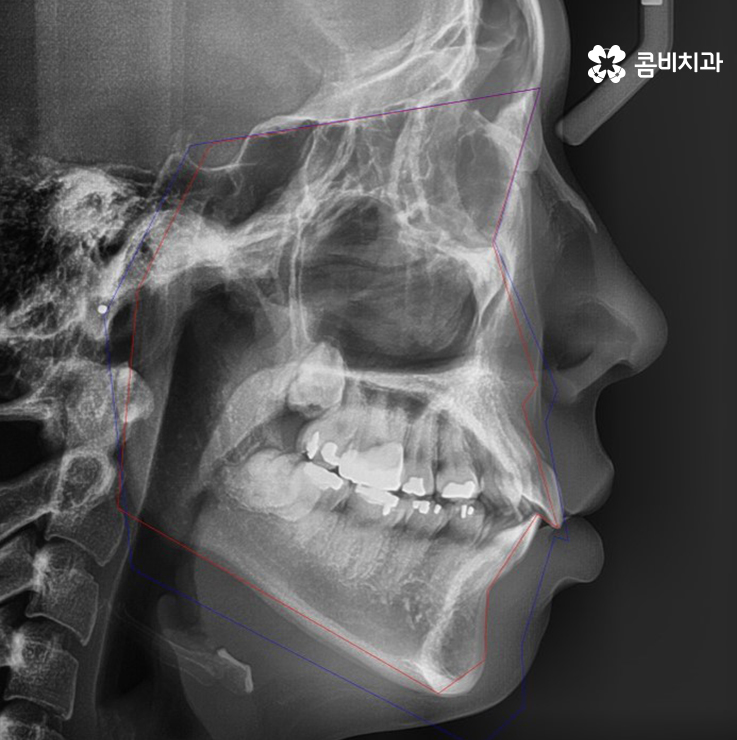

엑스레이에서 동그라미를 그린 4군데를 발치하여 교정이 진행된 사례

위 환자분의 사례는 현재 치열 상태와 골격, 얼굴형을 정밀

검진하여 시술 후 결과에 대한 시뮬레이션을 하였을 때

치열뿐 아니라 돌출입의 개선을 함께 목표로 진행이 되었기

때문에 콤비교정 전에 발치를 하게 된 케이스입니다.